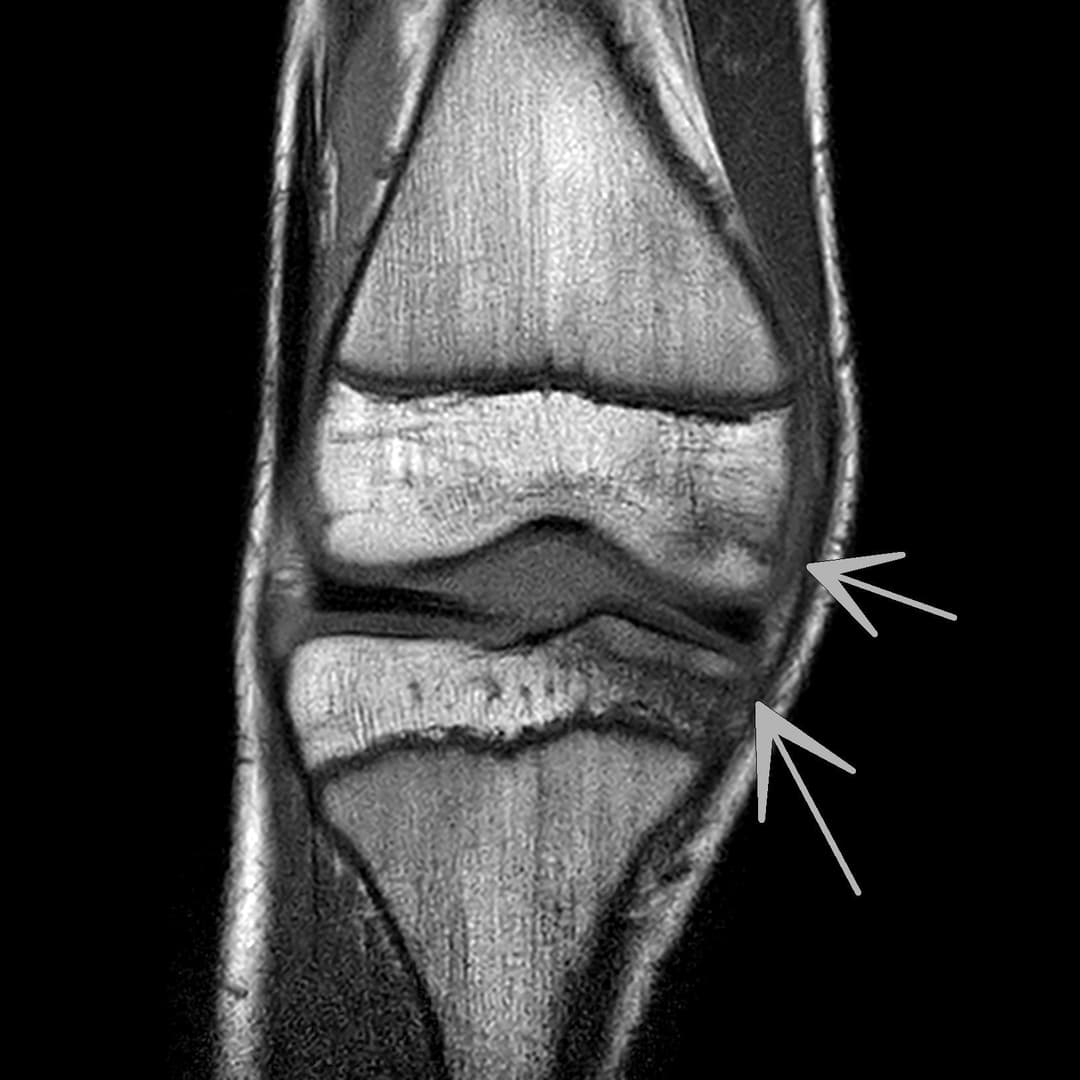

Contusion osteo-chondrale du genou

IRM

Intégrité ligamentaire et méniscale

Fracture sous chondrale par impaction avec œdème sous chondral en miroir du compartiment fémoro-tibial médial.

Epanchement articulaire abondant.